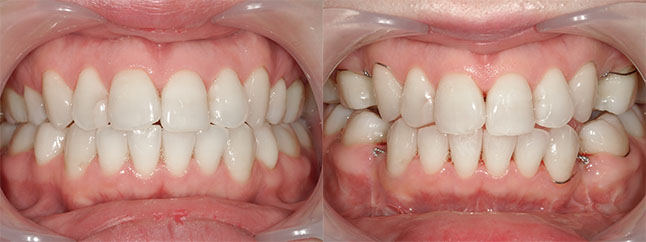

大阪府 22歳 女性

執刀医 辻和志

【治療内容】上のアゴと下のアゴの両方にこんもり感があったため、上下のアゴの骨をきって後ろに下げました。

【費用】上下セットバック 2,307,800円(税込)

【リスク】全身麻酔で行うため全身の健康状態が悪い方は行うことができません。また、手術当日は安静にしていただく必要があります。